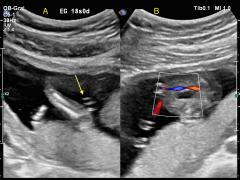

Se presenta el caso de una paciente de 23 años de edad, secundigesta, sin antecedentes personales ni familiares de relevancia. La paciente adjunta el estudio de screening de aneuploidías de la semana 11-14, que arroja bajo riesgo. Las imágenes 1 y 2 describen los hallazgos identificados durante la evaluación de la anatomía fetal en la semana 12. Las imágenes 3, 4 y 5 corresponden a los controles ecográficos posteriores, del segundo y tercer trimestre. La imagen 6 muestra al recién nacido.

Figura 1: se visualiza corte axial del abdomen fetal, a nivel de la inserción del cordón umbilical, con Doppler color en semana 12.

Figura 2: se observa corte axial, a nivel de la inserción del cordón umbilical en la pared abdominal anterior, en semana 12.

Figura 3: corte sagital a nivel de la inserción del cordón en la pared abdominal anterior, con Doppler color, en semana 20.

Figura 4: corte axial del abdomen fetal, en semana 32, donde se identifica dilatación de las asas intestinales.

Figura 5: corte axial del abdomen fetal, en semana 32, donde se identifica dilatación de las asas intestinales, con la utilización del Doppler color.